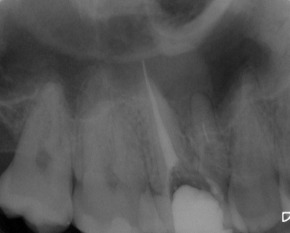

Nach Darstellung aller Wurzelkanaleingänge wird in einem zweiten Schritt das frakturierte Wurzelkanalinstrument dargestellt (Abb. 3 u. 4). Hierfür verwenden wir den Aufsatz 3E des Tigon+. Durch die schmale und lange Form des Instruments erreichen wir einen tiefen und schmalen Zugang.

Sofern es sich um ein kleines Frakturstück handelt, kann es durch aktive Übertragung von Energie des Ultraschalls zu einer Lockerung des Fragments kommen. Lockert es sich nicht, so „umkreist“ man das Instrument vorsichtig, um es anschließend mit einer Spritze gefüllt mit Palavit G zu greifen, zu fixieren und zu entfernen (Abb. 5). Nach Entfernung des Instruments erfolgt eine Kontrollaufnahme (Abb. 6).